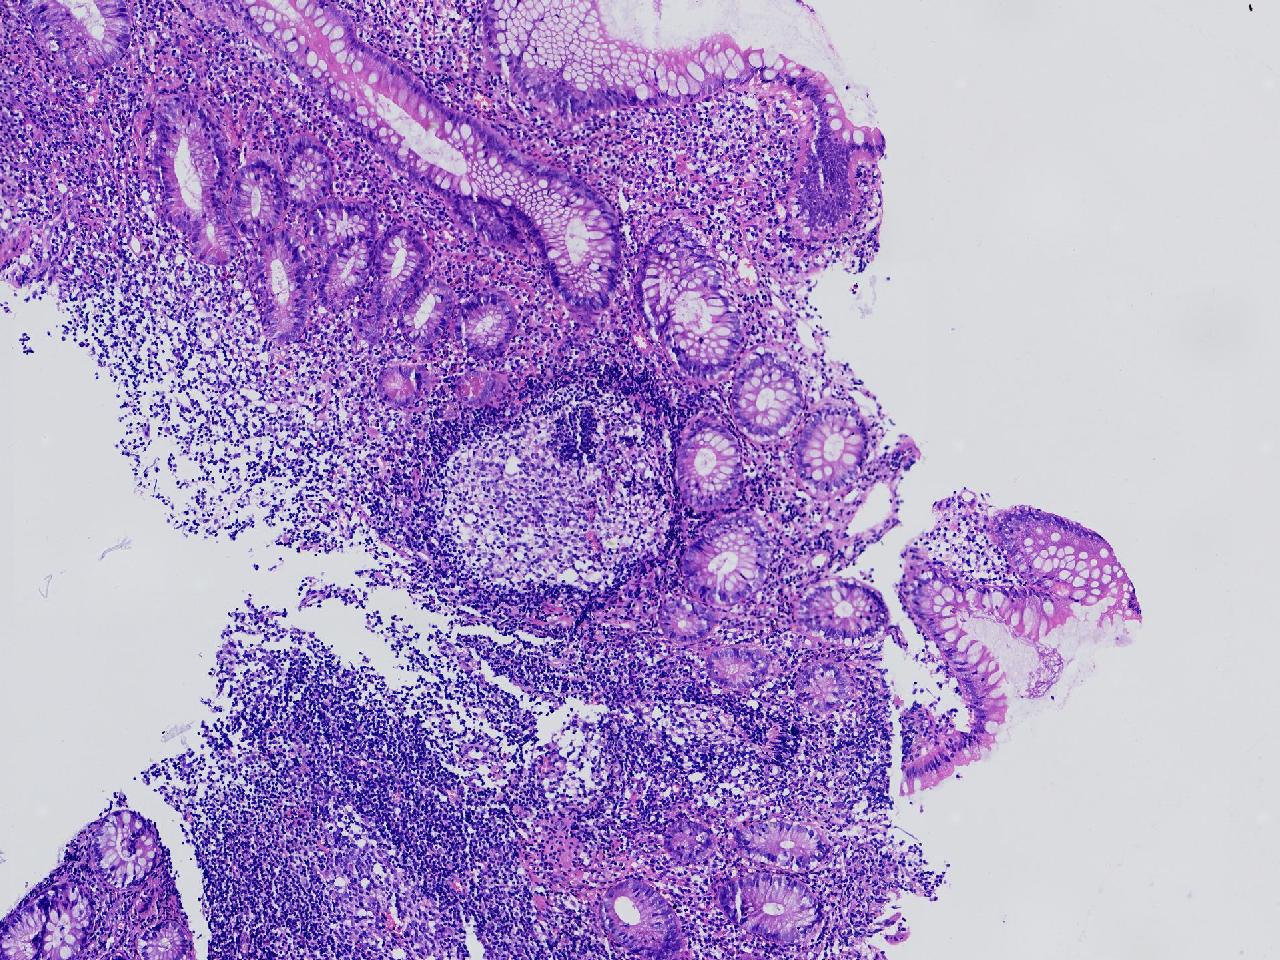

男,62岁,回盲部附近见多发片状溃疡,底覆薄白苔,周围粘膜充血水肿,活检2块,质软,弹性可。

回盲部活检

灰白色不整形软组织2块,直径均0.2厘米。

考虑:溃疡性结肠炎?

炎症性肠病要考虑,具体的类型不太好确定,需要结合临床。

上级医院会诊,不除外炎症性肠病,结合临床。